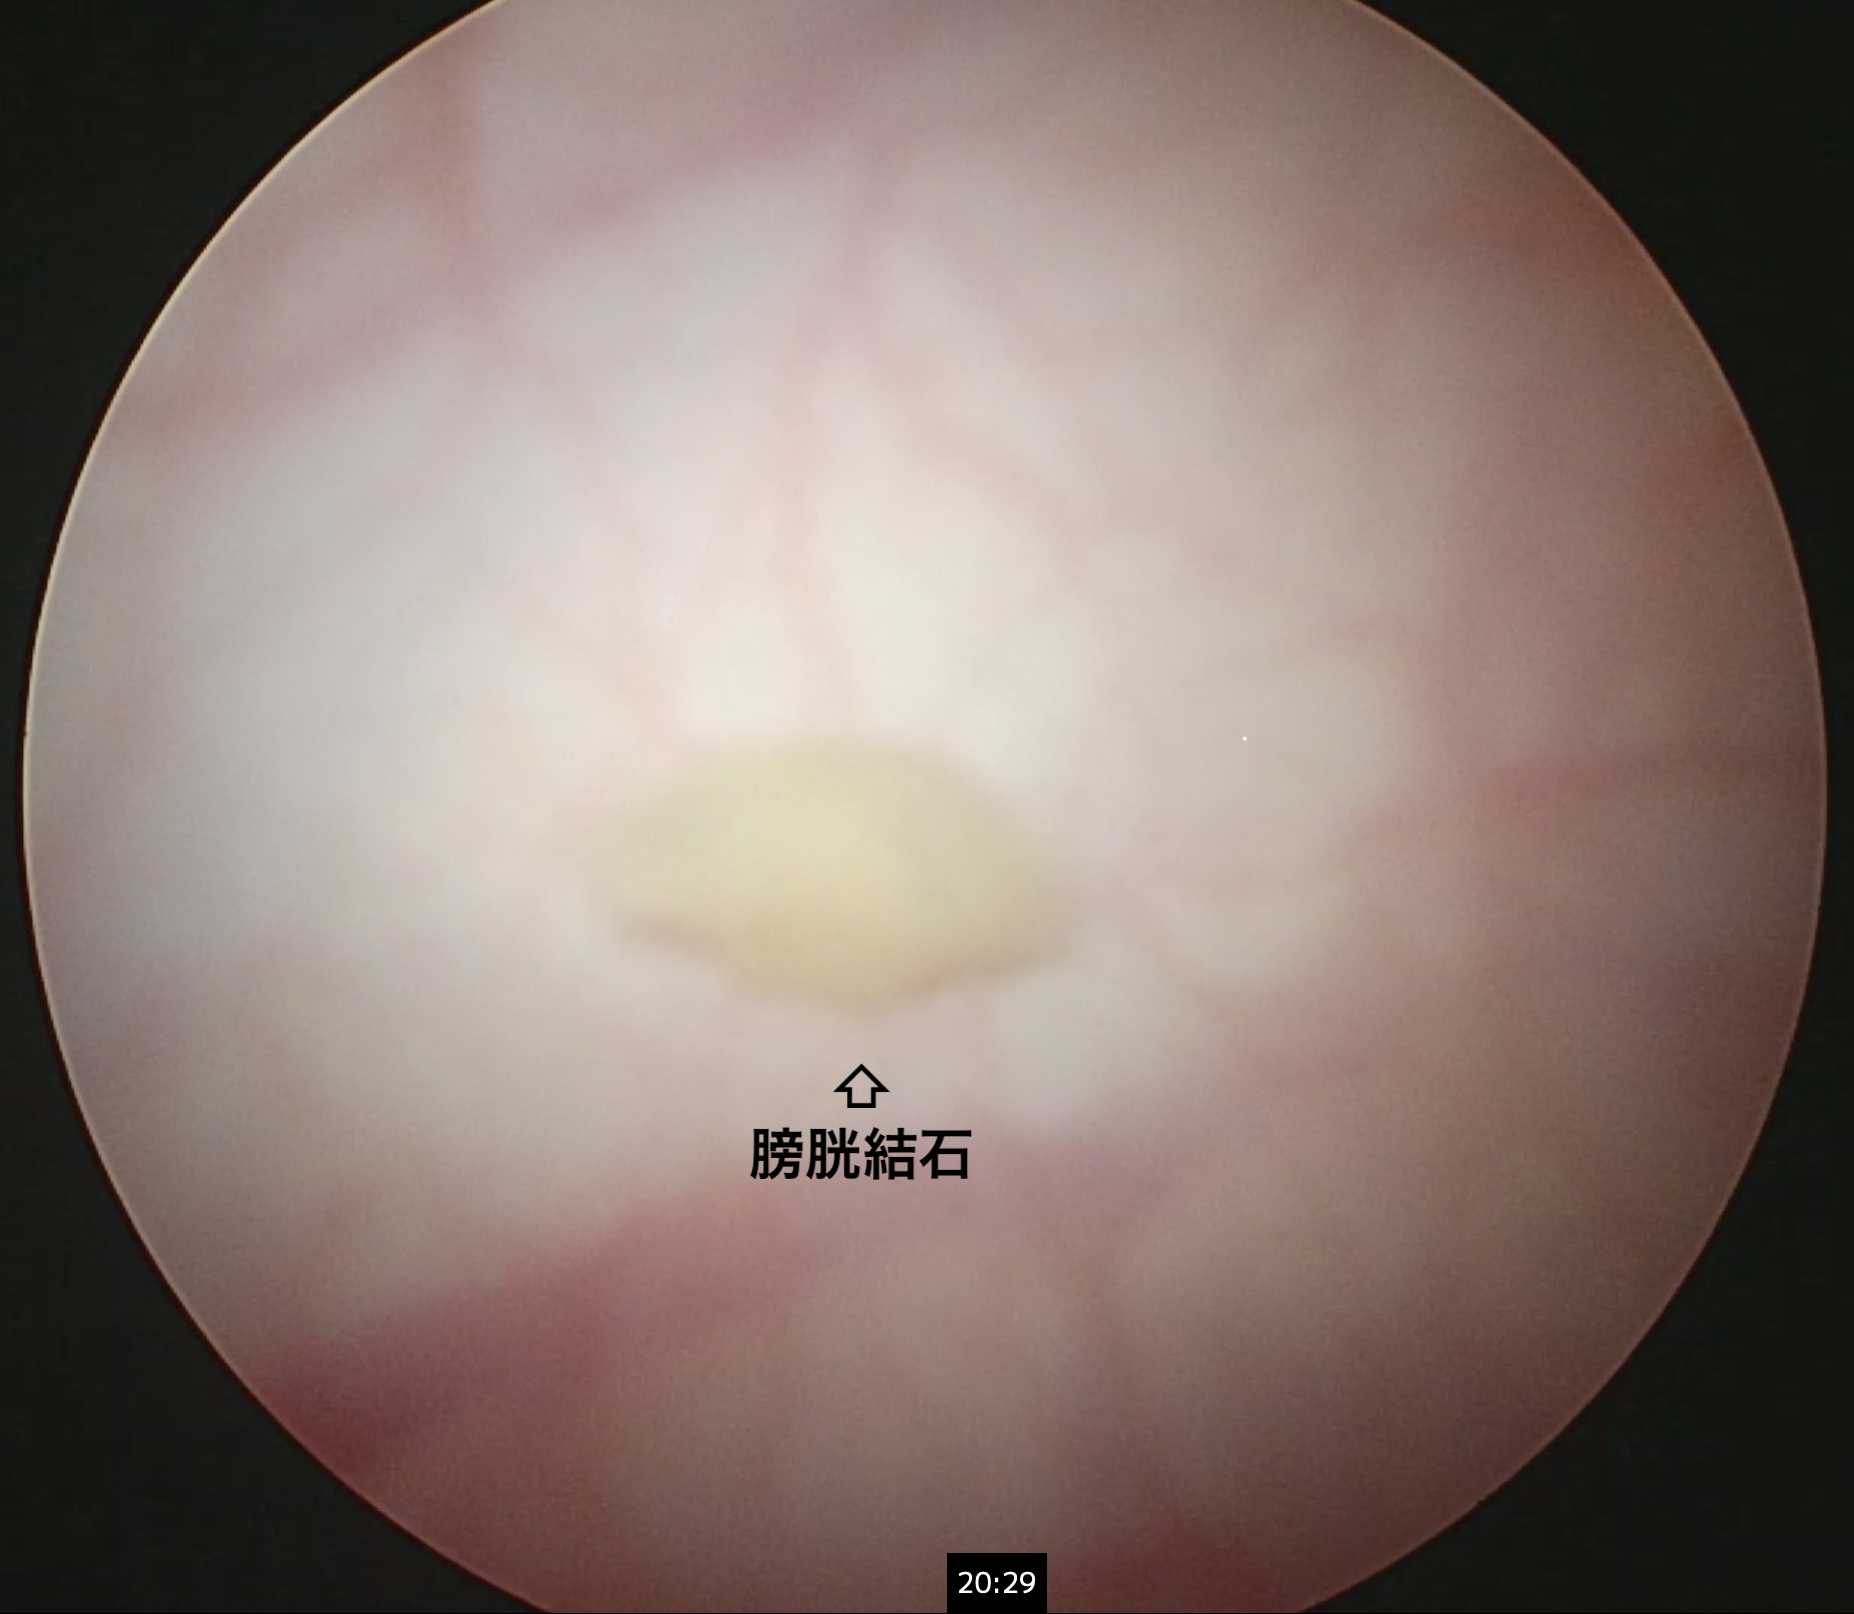

矢印は腹腔鏡カメラ越しに見た膀胱結石です。